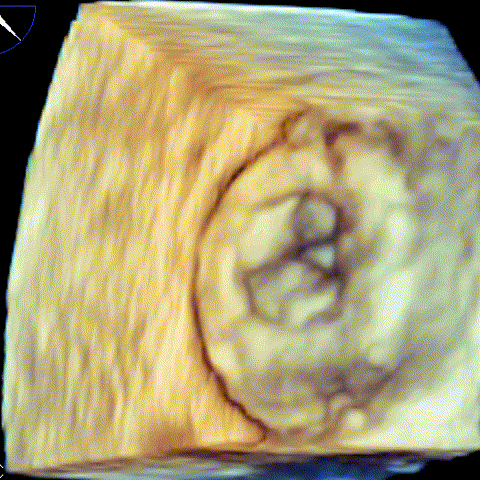

病例1 三维超声 病例1 三维超声

(瓣中瓣植入前) (瓣中瓣植入后)